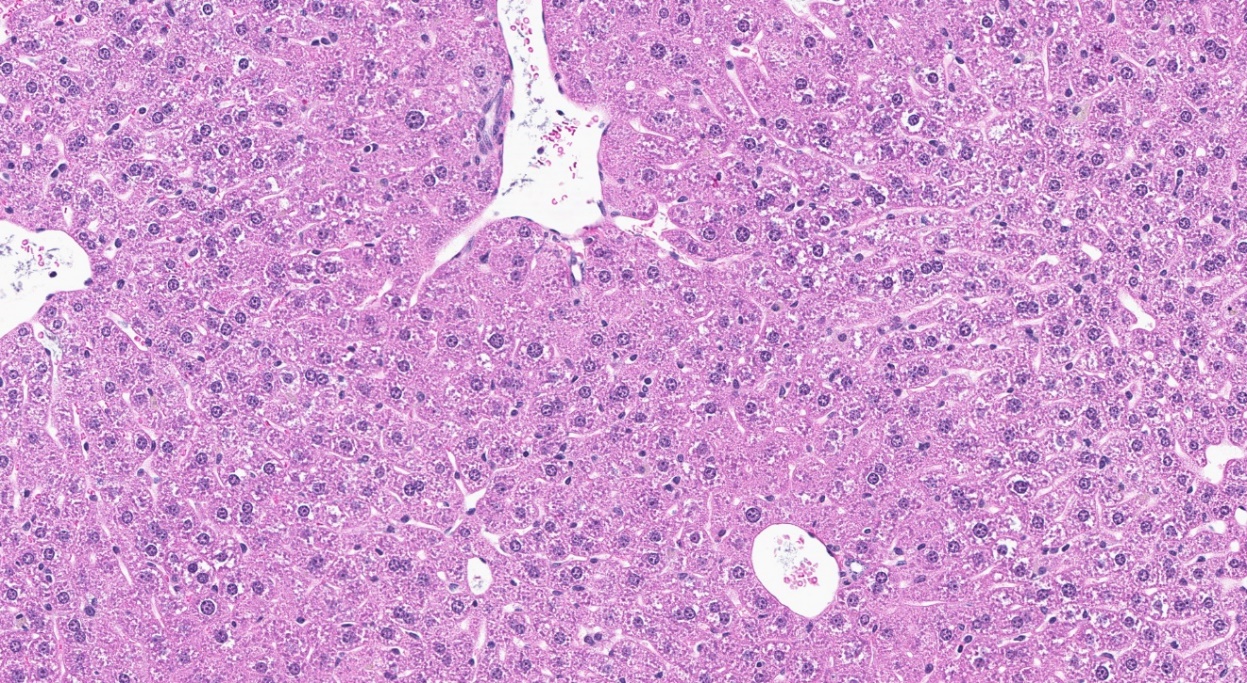

Two-year Study in Mice

The TCPP exposure groups were different for male and female mice exposed chronically. Exposure concentrations of TCPP in feed were 0, 1,250 (males only), 2,500, 5,000, or 10,000 (females only) ppm. An exposure concentration-related decrease in mean body weights was recorded in males and females relative to their respective control groups; however, survival, clinical observations, and feed consumption measurements were not suggestive of overt toxicity. Lower mean body weight was interpreted as a failure to gain weight. Similar to rats, mice also had a significant increase in liver neoplasms. Male mice had a significant increase in the incidence of hepatocellular carcinoma across all TCPP-exposed groups, but the incidences were similar among these groups. Significant increases in the incidence of hepatocellular adenoma, hepatocellular carcinoma, and hepatocellular adenoma or carcinoma (combined) were also noted in the 10,000 ppm TCPP-exposed female mice relative to the control females. Exposure-related nonneoplastic lesions were not observed in male mice. However, a significant increase in cytoplasmic alteration of hepatocytes was observed in nearly all females of the 10,000 ppm group. Additionally, a significant increase in eosinophilic foci was recorded in all female TCPP-exposed groups.